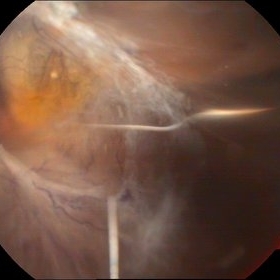

Rerinal Detachment with PVR

Sep 10 2014 by Mehul A Shah

A myopic male patient 35-years-old presented to outdoor and found to have retinal detachment with multiple fixed folds.

Photographer: Drashti Netralaya,Dahod

Imaging device: FF 450

Condition/keywords: proliferative vitreoretinopathy (PVR)